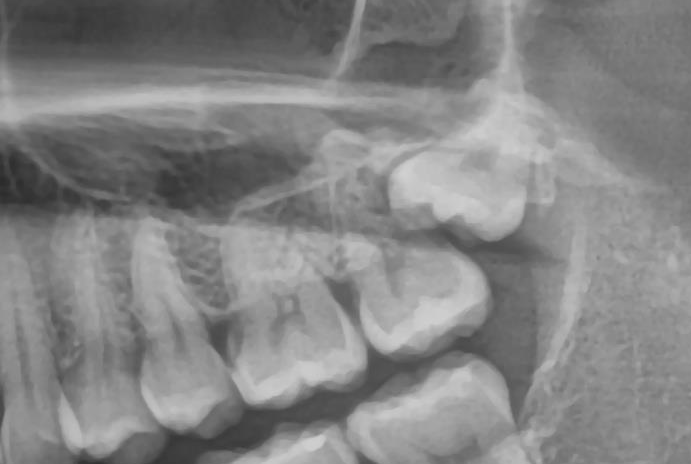

2. 잇몸 밖으로 일부만 나온 사랑니

부분 매복된 사랑니는

음식물과 세균이 쉽게 끼어 잇몸 염증과 통증이 반복될 수 있습니다.

특히 몸이 피곤할 때 잇몸이 붓고 아프다면,

사랑니 주위에 만성 염증이 있을 가능성이 큽니다.